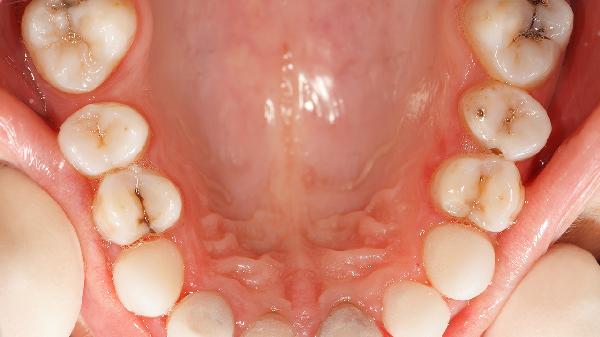

产生氟斑牙的常见原因主要有长期摄入过量氟化物、饮用高氟水、使用含氟牙膏不当、高氟地区生活、儿童牙齿发育期氟暴露等。氟斑牙是牙齿发育过程中因过量氟摄入导致的牙釉质矿化异常,表现为牙齿表面出现白垩色、黄色或褐色斑块。